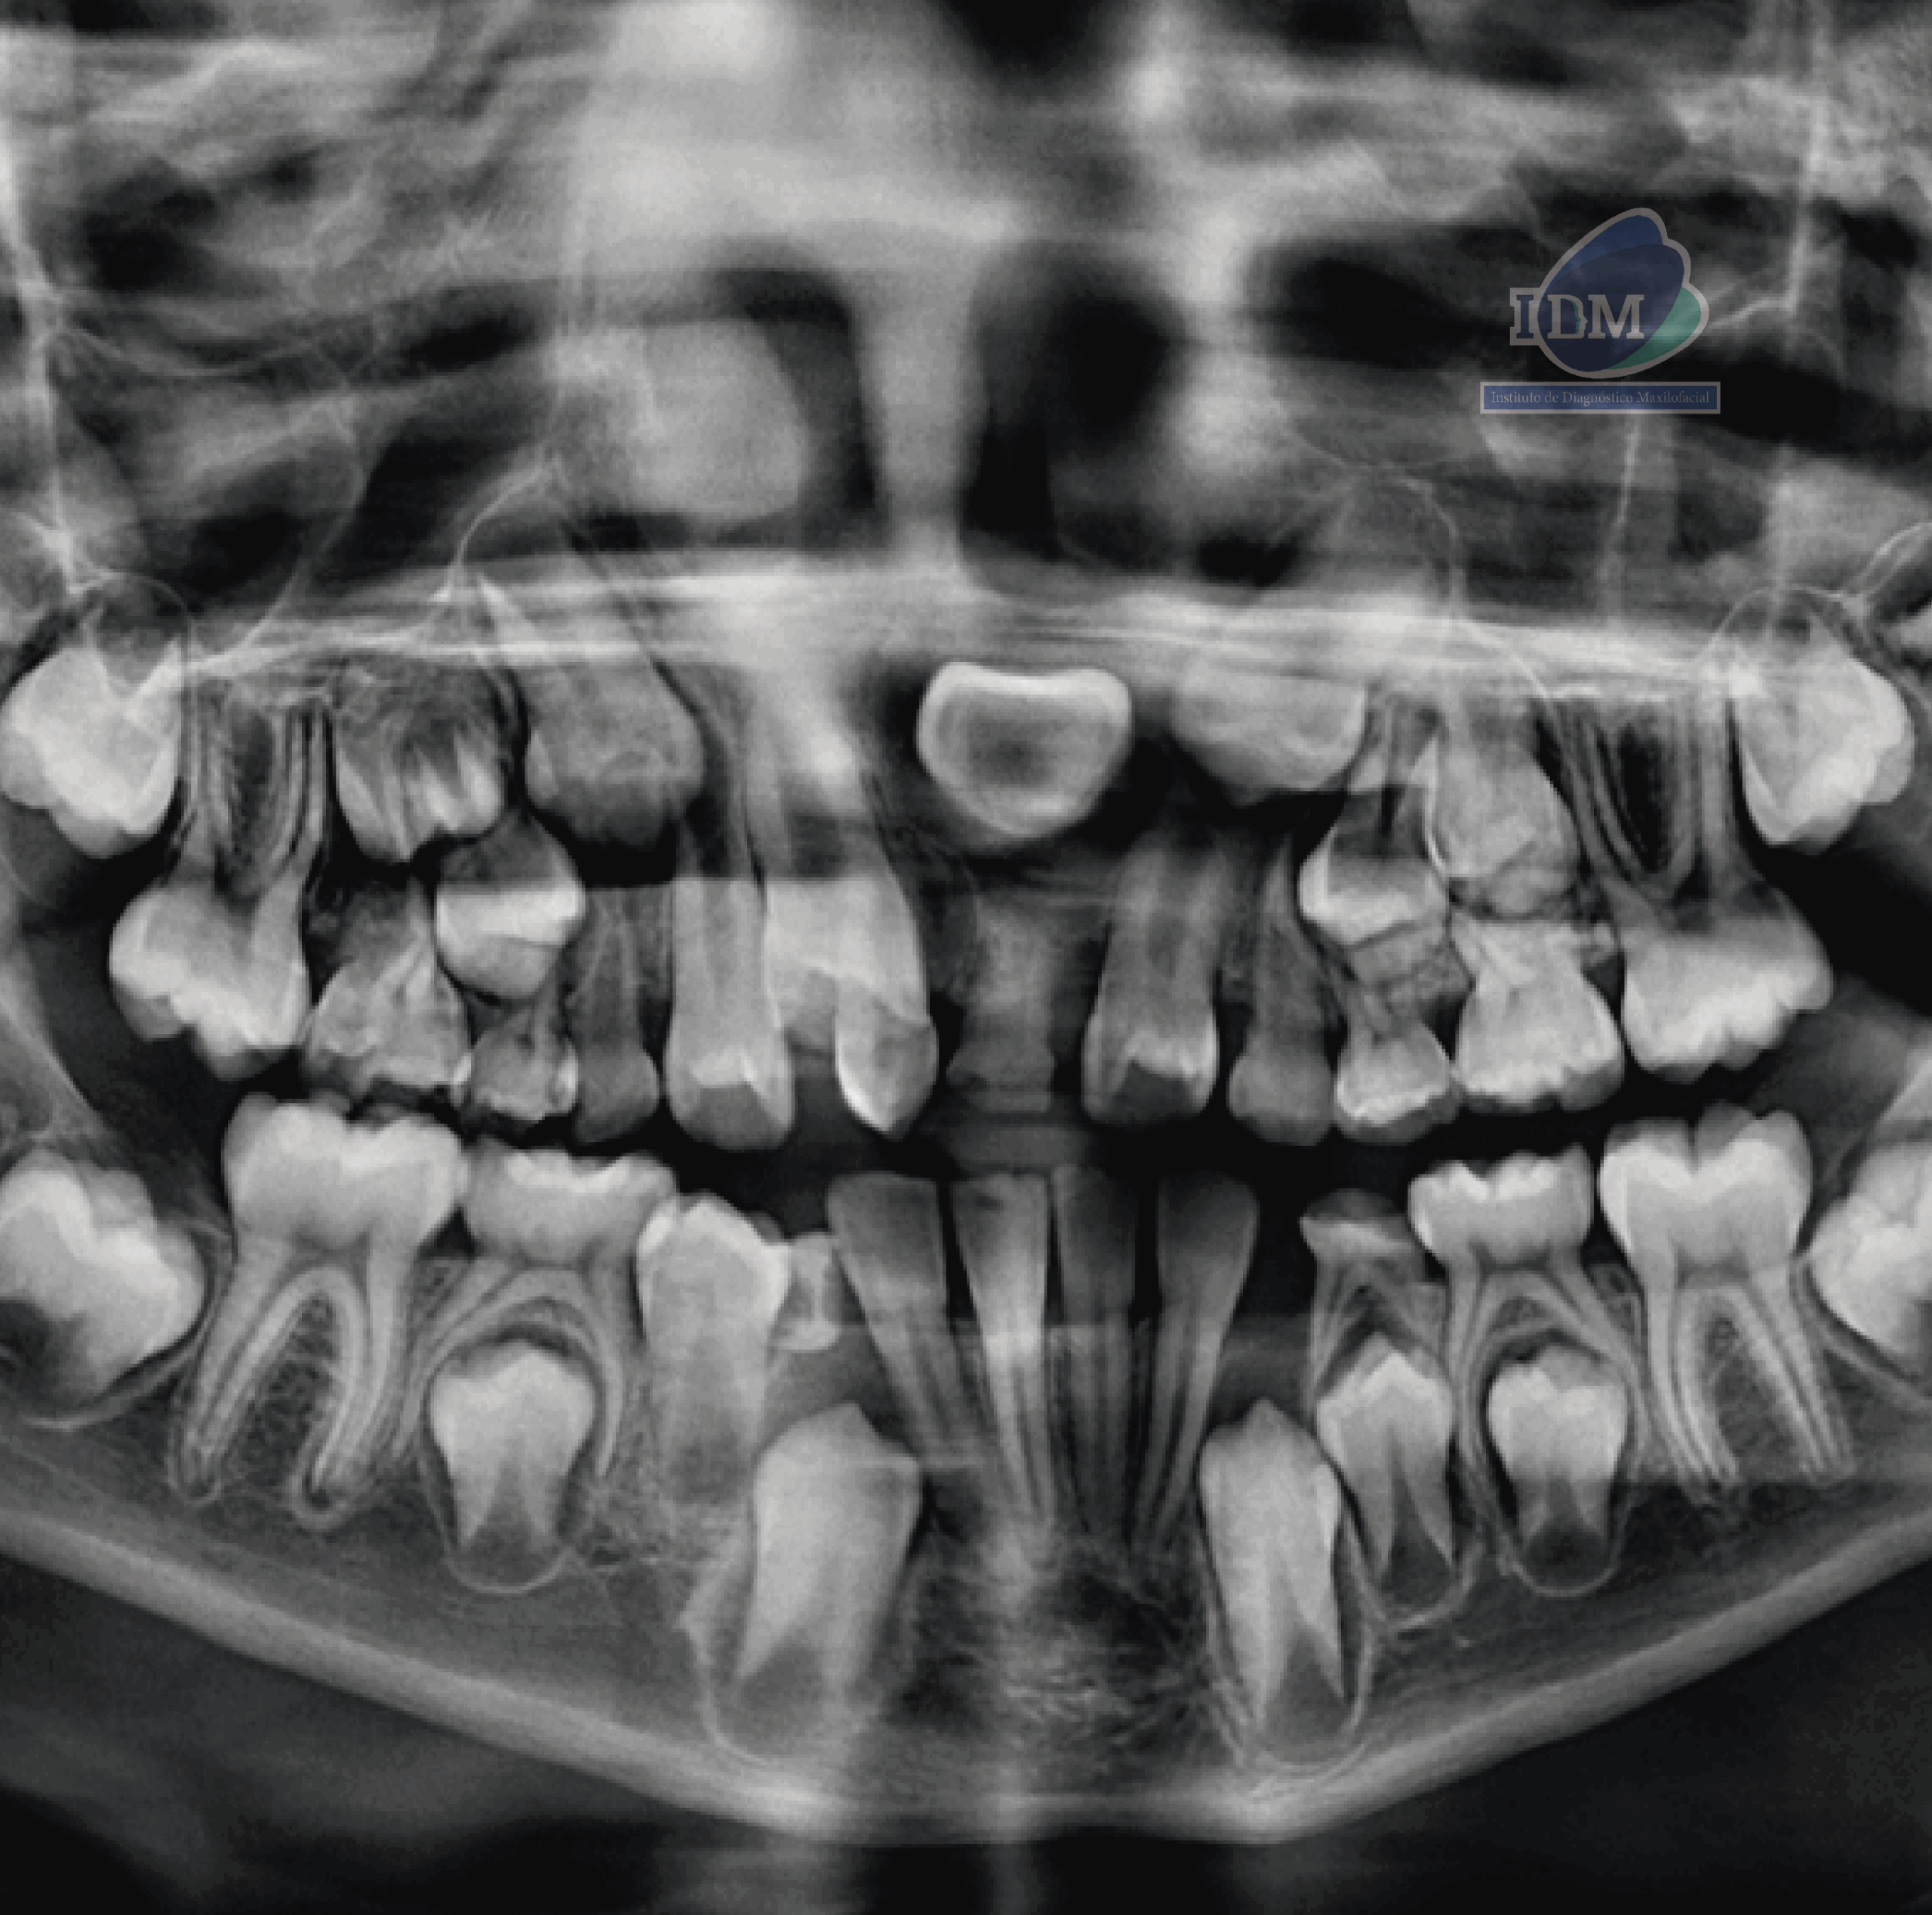

Radiografia Panorámica

A la evaluación de la radiografía panorámica se observa terceros molares en formación, múltiples piezas deciduas con lesiones cariosas, sin embargo, lo que llama la atención es la zona anterosuperior donde observamos la presencia de una pieza supernumeraria extraósea que ocasiona la impactación y el retraso en la erupción de la pieza 11, asimismo se observa la inclusión de la pieza 21 en posición transversal y la persistencia de la pieza 61.